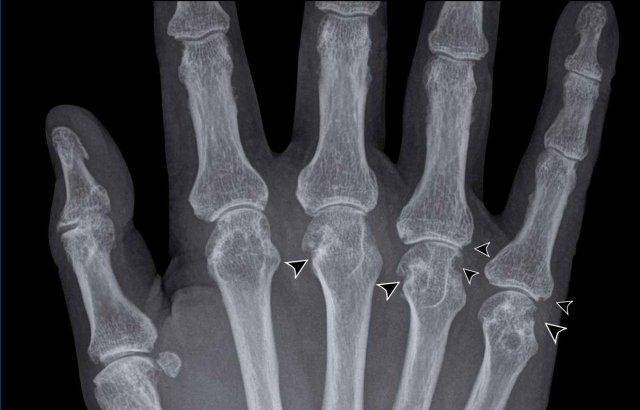

Trong trường hợp viêm khớp dạng thấp này, có hình ảnh bào mòn xương vùng rìa liền kề với hầu hết các khớp bàn ngón chân (MTP) (đầu mũi tên).

Khớp MTP thứ 5 là khớp bị tổn thương thường xuyên nhất trong viêm khớp dạng thấp.

Khi tình trạng bào mòn nặng nề như trong trường hợp này, hình ảnh có thể trông giống biến dạng “bút chì trong cốc” (mũi tên trắng) – dấu hiệu thường gặp trong viêm khớp vảy nến.

Tuy nhiên, phân bố tổn thương chủ yếu ở các khớp MTP và ít ảnh hưởng đến các khớp liên đốt là dấu hiệu gợi ý đây là trường hợp viêm khớp dạng thấp.